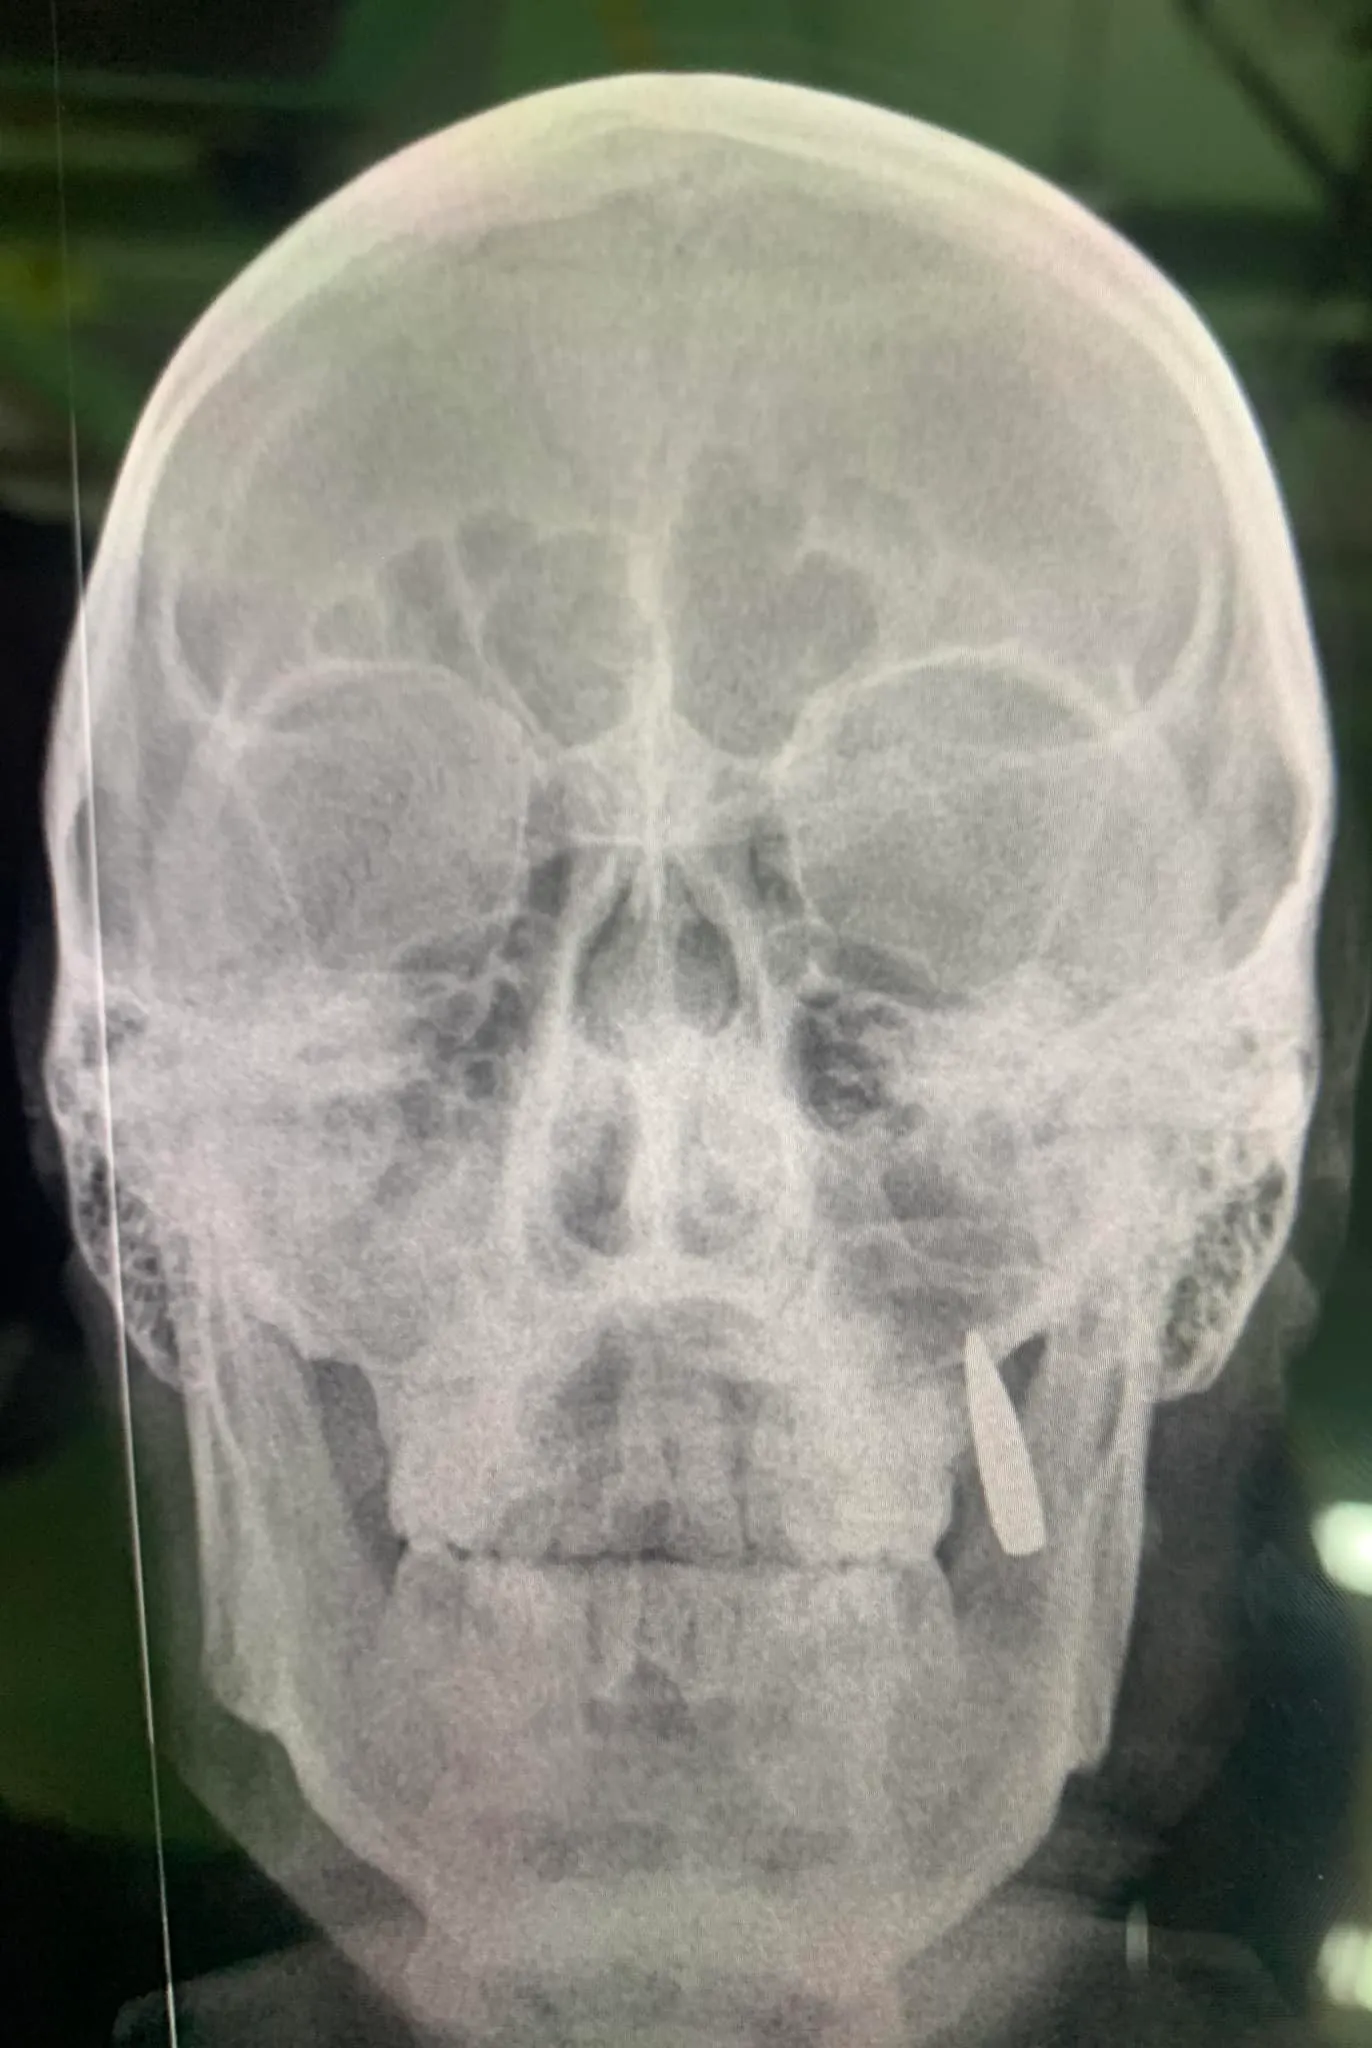

Делаем рентген. Вместо двух зубов, в челюсти застряла пуля. Ну так себе имплант,

– добавляет волонтер.

Также она опубликовала тот же рентгеновский снимок. И на нем действительно можно увидеть пулю в челюсти.

У бойца ВСУ в челюсти застряла пуля / Фото Оксаны Корчинской